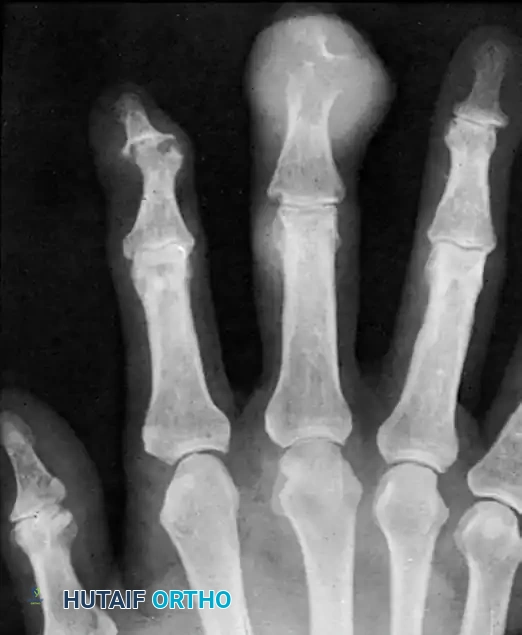

In advanced, poorly controlled gout, massive tophaceous deposits accumulate. These crystals trigger a profound inflammatory cascade, activating osteoclasts and inhibiting osteoblasts, leading to aggressive, localized bone resorption.

Radiographically, this manifests as well-defined, "punched-out" lytic lesions in the metaphysis and diaphysis, often with sclerotic margins and overhanging edges of cortical bone (Martel's sign). The sheer magnitude of bone destruction can easily mimic a primary lytic bone tumor or chronic osteomyelitis.